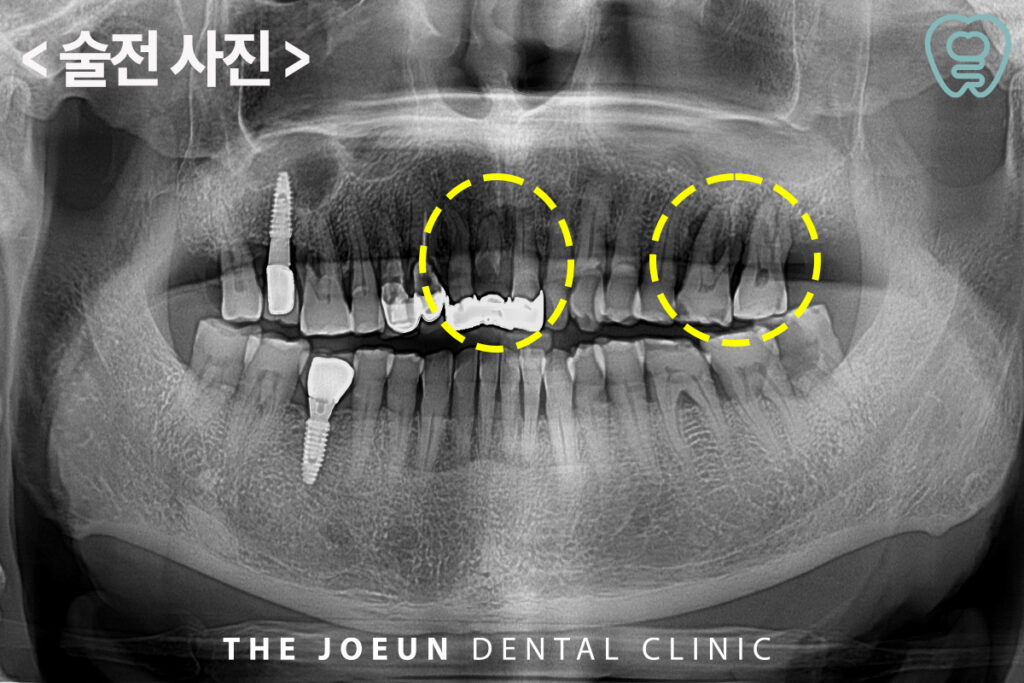

오늘은 뿌리까지 충치가 진행된 앞니와 어금니를 발치한 후 즉시 임플란트 식립을 진행하신 환자분을 소개해 드리려고 합니다. 환자분께서는 예전에 씌워둔 앞니가 흔들거리고 왼쪽 위 어금니도 씹을 때 통증이 느껴지신다며 치료를 위해 내원해 주셨습니다.

바로 눈으로 보기에도 뿌리까지 심하게 충치가 진행되어 까맣게 보이고 있었으며, 왼쪽 위 어금니의 경우에도 치아 뿌리 전체를 둘러싸고 있는 심한 염증으로 인해 살려서 쓰시기에는 무리가 있다고 판단되어 발치 후 임플란트 계획을 수립하였습니다.

잇몸뼈의 상태를 충분히 진단한 후 내원 당일 앞니와 어금니를 발치한 뒤 임플란트 식립을 진행하였습니다.